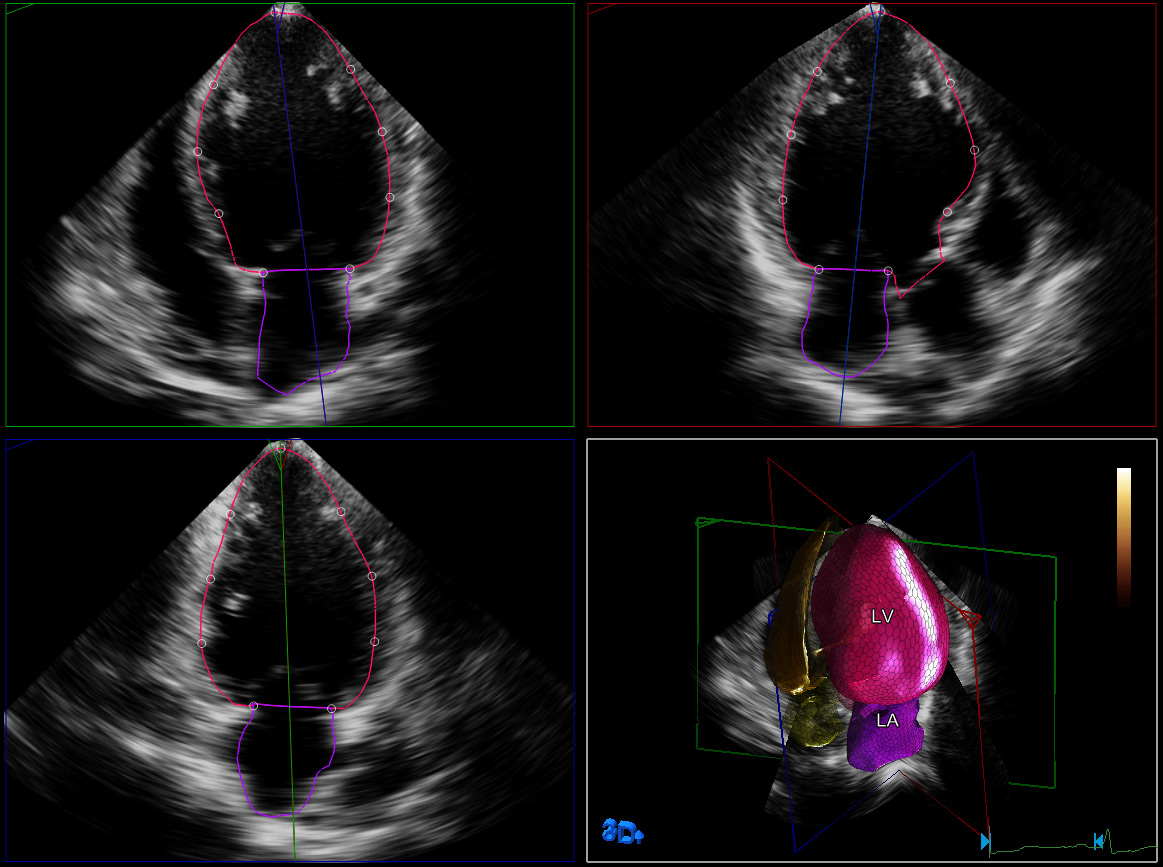

O HeartModelA.I. é uma ferramenta 3D que oferece uma fração de ejeção potente e reproduzível (EF) em poucos segundos. Esse aplicativo intuitivo e validado foi projetado para oferecer a confiança da quantificação cardíaca, que é perfeita para o fluxo de trabalho diário. O HeartModelA.I. oferece uma fácil e rápida quantificação 3D da câmara cardíaca, calculando simultaneamente os volumes do ventrículo esquerdo (LV, em inglês) e do átrio esquerdo (LA, em inglês) em um único ciclo volumétrico. Além de oferecer a quantificação do LV, o HeartModelA.I. é a única ferramenta validada a apresentar volumes simultâneos do LA. Ela possibilita a fácil caracterização do volume do LA para obter mais informações clínicas, sem qualquer etapa ou tempo adicional. O volume do LA demonstrou ser um indicador de resultados cardiovasculares.

Este estudo comparou a quantificação entre o HeartModelᴬ×ᴵ× 2D e o 3D ao vivo, demonstrando uma economia de tempo de 82% quando o HeartModelᴬ×ᴵ× usou o recurso automatizado e uma economia de tempo de 63% quando ele precisou de mínimas modificações.

O estudo multicêntrico de Medvedofsky et almostra que a ressonância 3D com o HeartModelA.I. é precisa e reproduzível.